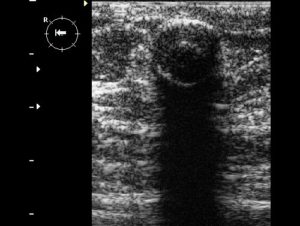

Гипоэхогенное образование на мониторе ультразвукового аппарата выглядит как затемненное пятно. Его форма различна, зависит от типа уплотнения. Контур может быть смыт или четко виден.

При осмотре молочных желез с помощью аппарата УЗИ в В-режиме мы получаем черно-белую картинку, демонстрирующую структуры органа с разной способностью отражать ультразвуковой сигнал:

- анэхогенные структуры — это буквально черные пятна на УЗ-снимке;

- гипоэхогенные — темно-серые образования с большой гидрофильностью;

- средней эхогенности или эхопозитивные структуры дают на снимке серый цвет;

- образования повышенной эхогенности — светло-серые на снимке ткани высокой плотности;

- гиперэхогенные образования — ярко-белые, УЗ-сигнал от таких структур полностью отражается, за ними обычно есть акустическая тень.

Гипоэхогенность объекта в молочной железе зависит от акустической плотности ее ткани. На снимке он будет выглядеть как область с темным цветом. В этом участке высокочастотный звук движется гораздо медленнее, чем в любом другом пространстве. Эти характеристики чаще всего имеет объект, наполненный жидкостью.